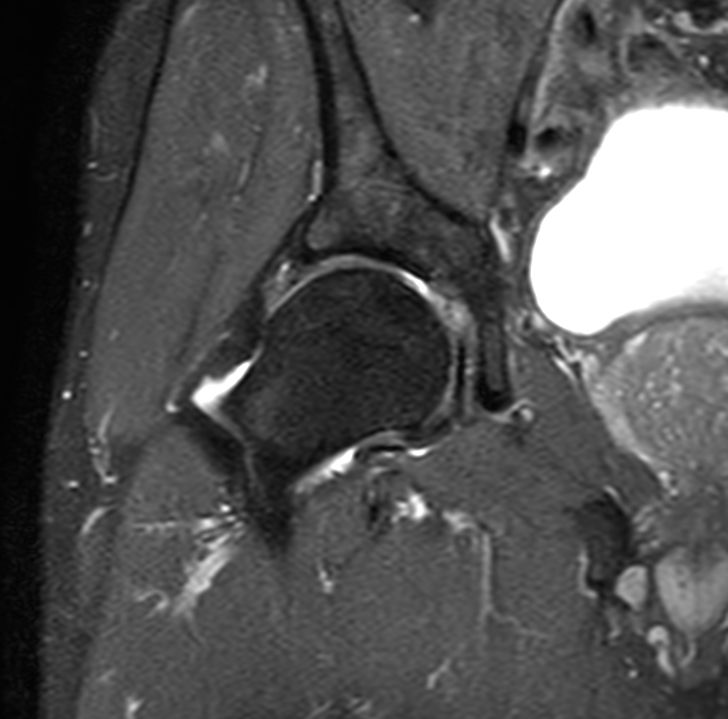

Coronal PDw TSE FatSat

-